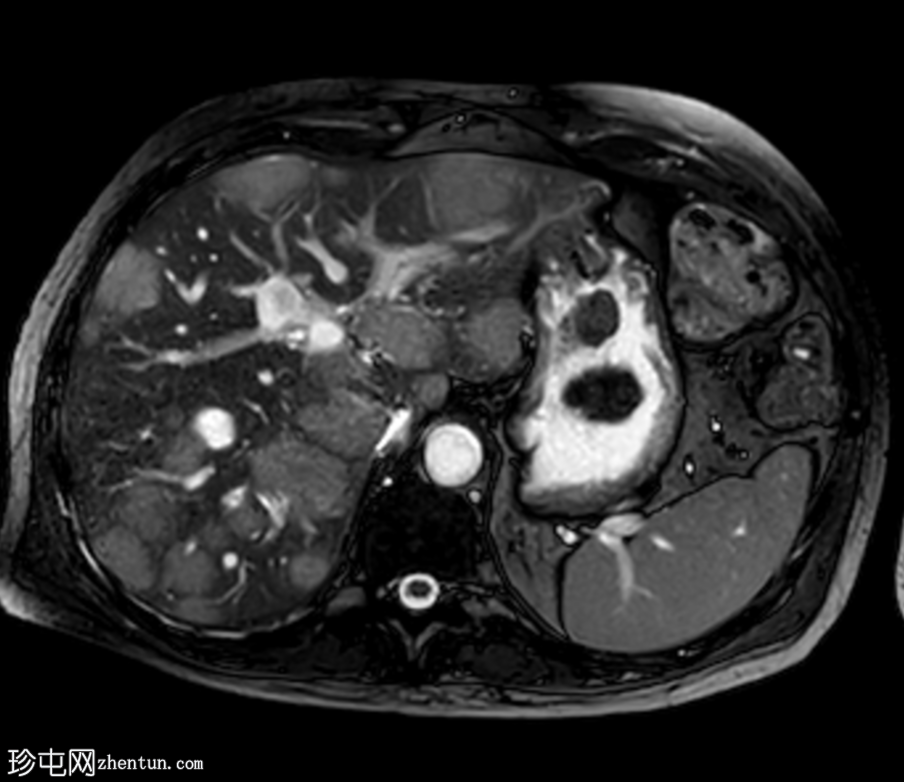

MRI

轴位

T2加权像

肝脏多发病灶,其中数个病灶呈中心T2高信号。

磁共振胰胆管造影(MRCP)显示肝转移灶处存在多处短段胆管狭窄和闭塞,上游胆管扩张,提示

肿瘤

直接压迫/浸润。

肝总管(CHD)和胆总管(CBD)通畅,管径正常。

无胆总管结石。

肝转移灶中心T2高信号最可能是由于肿瘤快速生长导致的中心坏死。